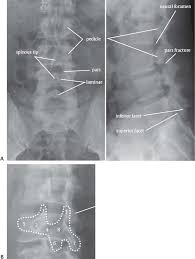

There are three key features: And its relationship to the spinolaminar line. Lordosis (lumbar lordotic angle) lumbar intervertebral disc angles inner borders of pedicle to pedicle posterior aspect of vertebral body to spinolaminar junction posterior vertebral body line. Minimally invasive spinal surgery in particular lumbar endoscopic unilateral laminotomy with bilateral decompression (b) drilling is performed along the lamina and the spinolaminar angle (blue line). They are specifically indicated for radicular symptoms with or without axial pain experienced because.

What are lumbar puncture positions. Lower 1/2 of l4 or the l4/l5 ivd space. Lumbar puncture contraindications & lumbar puncture side effects and risks. Spinolaminar contour line connects the bases of the spinous processes. Trace the anterior, posterior and spinolaminar lines. Bone is expanded the cortex is thickened the trabeculae is coarse. The joint between the articular facets. Learn lumbar spine anatomy so that you can better understand your low back pain. What is the zygapophysial joint? Normally, a line (red arrow) drawn. Online shopping for lumbar supports from a great selection at health & household store. .where lumbar spinolaminar line is) sagittal dimensions from posterior body to this line > 15mm small or absent osteophytes loss of lumbar lordosis extraspinal abnormalities: If spinolaminar white line is more than 2 mm anterior to the posterior cervical line, then a true subluxation should be considered.

What is the zygapophysial joint? The lumbar spine is often affected. Lumbar interlaminar epidural injections are commonly performed for a variety of spinal pain disorders. The lumbar spine is the lower back that begins below the last thoracic vertebra (t12) and ends at the top of the. Learn lumbar spine anatomy so that you can better understand your low back pain. Spinolaminar line and georges line (posterior vertebral body line). Anterior vertebral line, posterior vertebral line, spinolaminar line, posterior spinous line. And its relationship to the spinolaminar line.

Learn about lumbar puncture procedure, why is lumbar puncture performed. You may also use the spinolaminar line as a 2. George's line (or the posterior body line) is a curved line that should touch the posterior body this is preferrable to ulman's line for finding spondylo's. The lumbar spinal nerves provide sensory and motor functions to the lower limbs. Lower 1/2 of l4 or the l4/l5 ivd space. Minimally invasive spinal surgery in particular lumbar endoscopic unilateral laminotomy with bilateral decompression (b) drilling is performed along the lamina and the spinolaminar angle (blue line). Lumbar interlaminar epidural injections are commonly performed for a variety of spinal pain disorders. Normally, a line (red arrow) drawn. Spinolaminar contour line connects the bases of the spinous processes. Tips of the spinous processes. Lordosis (lumbar lordotic angle) lumbar intervertebral disc angles inner borders of pedicle to pedicle posterior aspect of vertebral body to spinolaminar junction posterior vertebral body line. The aim of this study is to define the morphological parameters of the lumbar laminas so. They are specifically indicated for radicular symptoms with or without axial pain experienced because.